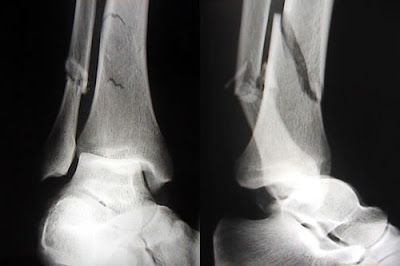

Luego que experimentamos una fractura hay varios pasos para lograr un buen proceso de curación ya que como resultado de la fractura los vasos sanguíneos que atraviesan la línea de la fractura se rompen.

Estos vasos se alojan en la cavidad medular, en los sistemas de Havers (osteomas) y en el periostio.

Por causa de esas rupturas de los vasos la sangre se comienza a alojar y se acumula en los extremos lesionados de los vasos formándose así un coagulo alrededor de la fractura y de la misma.

A este coagulo se le llama hematoma de la fractura y generalmente se hace presente después de las ocho horas de la fractura

Como al romperse los vasos sanguíneos la circulación se detiene a causa del hematoma que se forma, eso causa la muerte de las células óseas y de las células periosticas.Si no es necesario el injerto óseo, la fractura se puede reparar de diferentes formas. Insertando uno o más tornillos a través de la ruptura para sostener el hueso. Perforando y fijando una placa de acero sostenida por tornillos en el hueso. O introduciendo un clavo metálico largo y grueso.